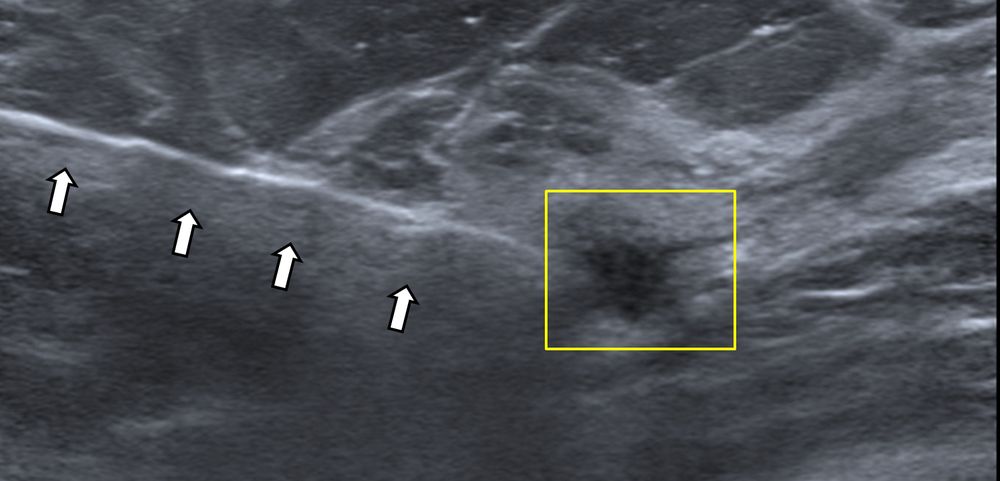

- Υπερηχογραφικά καθοδηγούμενη βιοψία μαστού - core biopsy

Εχει αντικαταστήσει την FNA στις συμπαγείς βλάβες του μαστού, γιατί η ποσότητα του ιστού που συλλέγεται είναι μεγαλύτερη και το αποτέλεσμα πιο αξιόπιστο.